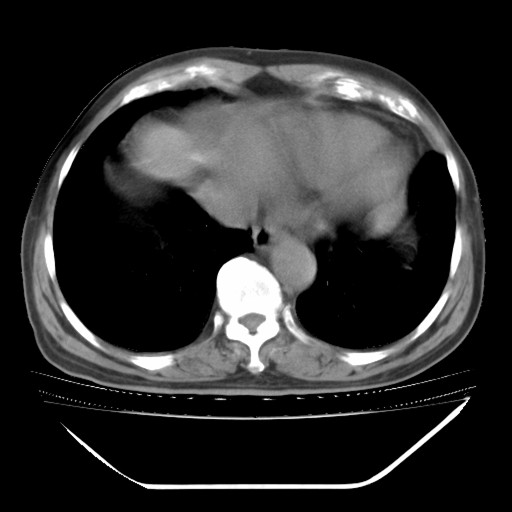

以下是引用hhcckk在2009-5-29 10:34:00的发言:[br]左下肺片絮状边缘模糊影,考虑感染,建议治疗后复查[br]